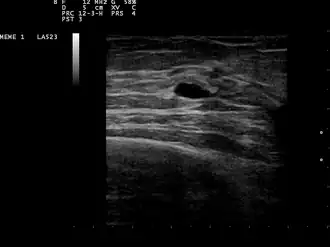

![]() Pequeño quiste mamario. Ecografía. | ||

La naturaleza quística de un bulto mamario se puede confirmar mediante ecografía, aspiración [8] (extracción del contenido con aguja) o mamografía. La ecografía también puede mostrar si el quiste contiene nódulos sólidos, señal de que la lesión puede ser precancerosa o cancerosa. El examen realizado por un citopatólogo del líquido aspirado del quiste también puede ayudar con este diagnóstico. En particular, debe enviarse a un laboratorio para que se analice si está manchado de sangre.

A las pacientes con sospecha de quistes mamarios normalmente se les realizará una mamografía de diagnóstico, aunque no se sospecha que tengan cáncer. Este tipo de mamografía brinda al médico la posibilidad de realizar una ecografía mamaria al mismo tiempo y es por eso que muchas veces se prefieren a las mamografías de detección. La ecografía mamaria se considera la mejor opción a la hora de diagnosticar quistes mamarios porque tiene una precisión del 95 al 100%, proporciona una imagen clara de la apariencia del quiste (simple o complejo) y también puede distinguir entre bultos sólidos y quistes llenos de líquido, que la mamografía no puede hacer. [9] Las ecografías mamarias se realizan con la ayuda de un instrumento médico de mano que se coloca sobre la piel, después de que se le haya aplicado un tipo de líquido especial. Los instrumentos captan el eco resultante de las ondas sonoras que envía al pecho. Estos ecos se transmiten a una computadora que los traduce en una imagen.